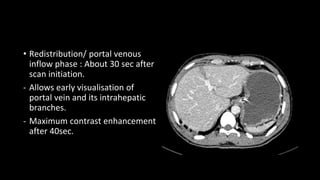

• Redistribution/ portal venous

inflow phase : About 30 sec after

scan initiation.

- Allows early visualisation of

portal vein and its intrahepatic

branches.

- Maximum contrast enhancement

after 40sec.

• Redistribution/ portalvenous inflow phase : About 30 sec after scan initiation. - Allows early visualisation of portal vein and its intrahepatic branches. - Maximum contrast enhancement after 40sec.